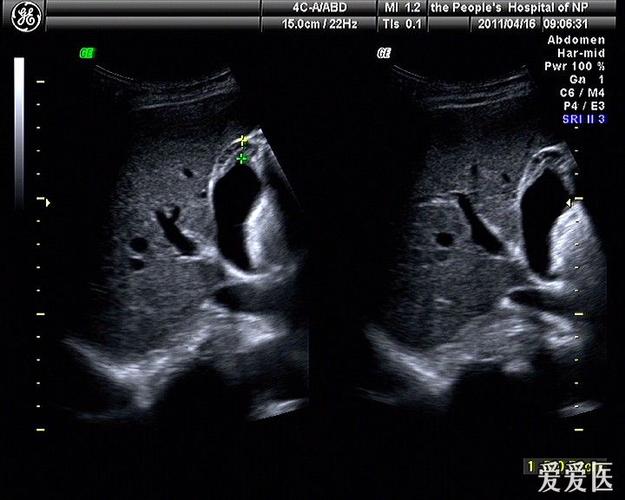

胆囊腺肌症超声表现

胆囊腺肌症超声表现,胆囊腺肌症超声报告

大家看看这个胆囊,可以考虑腺肌症吗

胆囊腺肌症可能,请指教

胆囊腺肌症彩超图片

胆囊腺肌症超声图片

胆囊腺肌症超声

胆囊腺肌症图片彩超